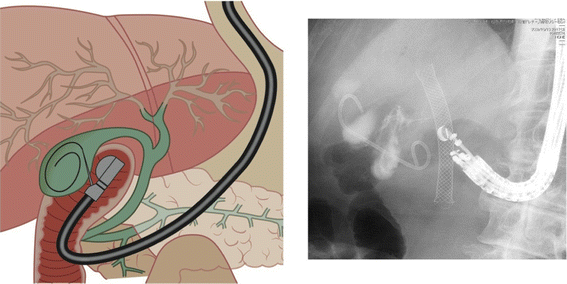

EUS-guided gallbladder drainage is performed via the antrum of the stomach and bulbus of the duodenum (Fig. 5) [16, 42]. It includes EUS-guided naso-gallbladder drainage [37, 38] and EUS-guided gallbladder stenting [39, 44] (Table 2). Recently one controlled study [42] showed that EUS-GBD is comparable to PTGBD in terms of the technical feasibility and efficacy. However, EUS-guided gallbladder drainage has not been established as a standard method. Therefore, they should be performed in high-volume institutes by skilled endoscopists [37–46].

Fig. 5

EUS-guided gallbladder approach via bulbus of the duodenum. Left Schema of EUS-guided gallbladder drainage. Right X-ray shows double-pig tail stent placed in the gallbladder

Technique of EUS-guided gallbladder drainage [16, 44] (Video 3)

Theoretically, the gallbladder does not have adhesions to the GI tract. Therefore, there is a possibility of bile leakage during the procedures; in particular, if the procedure fails, serious bile peritonitis can occur. The choice of endoscope position is important to accomplish the procedure safely. The gallbladder is visualized from the duodenal bulb or the antrum of the stomach using a curved linear array echoendoscope in a long scope position (pushing scope position) (Fig. 5). At this time, the direction of the EUS probe is toward the right side of the body. A needle knife (Zimmon papillotomy knife, or Cystotome, Wilson-Cook, Winston-Salem, NC, USA) catheter using electrocautery, or a 19-gauge needle (EchoTip, Wilson-Cook), is advanced into the gallbladder under EUS visualization after confirming the absence of intervening blood vessels to avoid bleeding. After the stylet has been removed, first bile is aspirated and then contrast medium is injected into the gallbladder for cholecystography, then a 0.025- or 0.035-in. guidewire is advanced into the outer sheath. If necessary, a biliary catheter for dilation (Soehendra Biliary Dilator, Wilson-Cook), or papillary balloon dilation catheter (Maxpass, Olympus Medical Systems) are used for dilation of the gastrocholecystic and duodenocholecystic fistula. Finally, a 5-10 Fr naso-gallbladder tube is advanced via the cholecystogastrostomy and cholecystoduodenostomy site into the gallbladder. The basic procedure of EUS-guided gallbladder stenting is the same as EUS-guided naso-gallbladder drainage. A 7-10Fr double pigtail plastic or self-expanding metallic stent is placed in the final step.